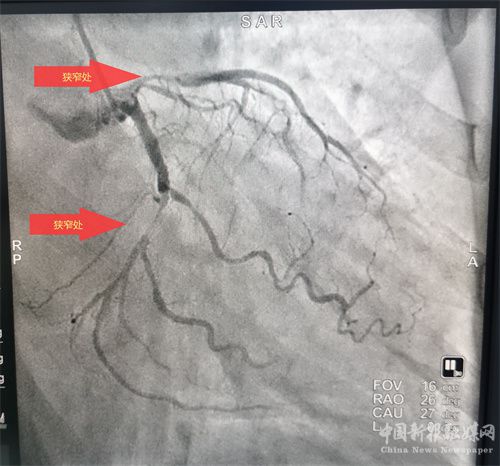

患者溶栓成功后,經(jīng)患者及家屬同意后行冠狀動(dòng)脈造影檢查,患者冠脈顯示前降支次全閉、回旋支狹窄95%、右冠近端狹窄85%,病情緊急,李維軍、楊亮主任向家屬詳細(xì)講明病情后,予以開(kāi)通前降支和回旋支,植入支架3枚。手術(shù)全程用時(shí)不到一個(gè)小時(shí)。目前,患者病情穩(wěn)定。